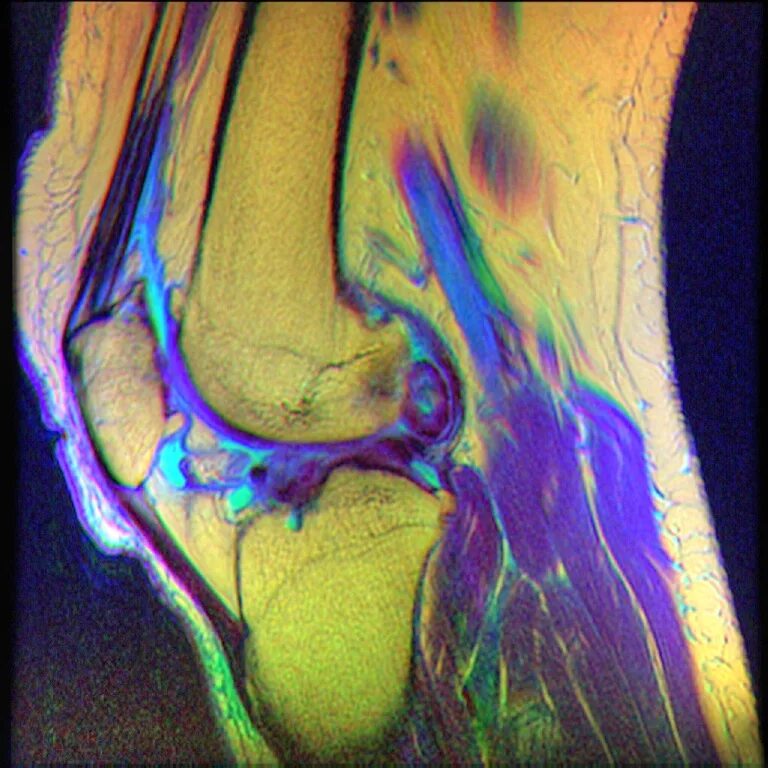

Пигментный виллонодулярный синовит